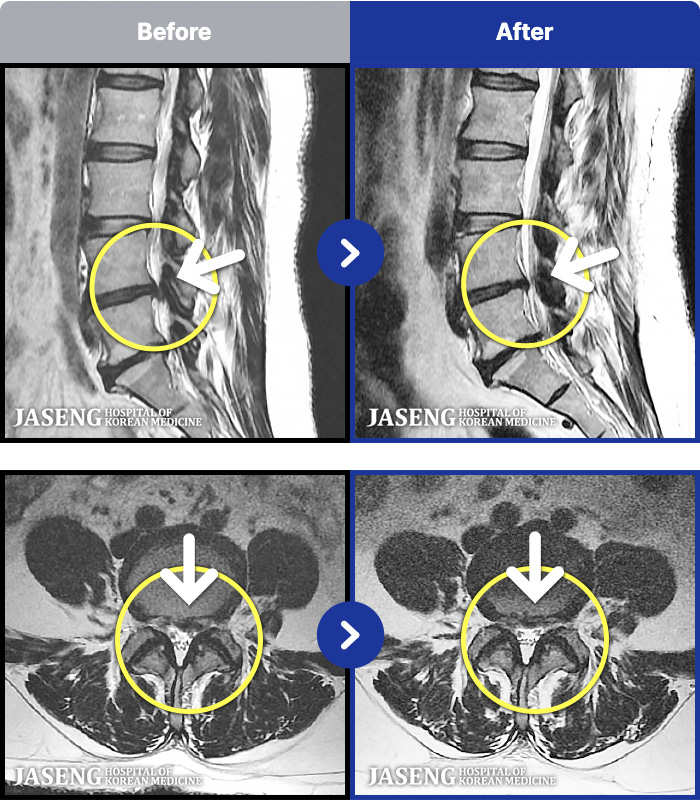

55 MRI ũ ʸ Ȯϼ.